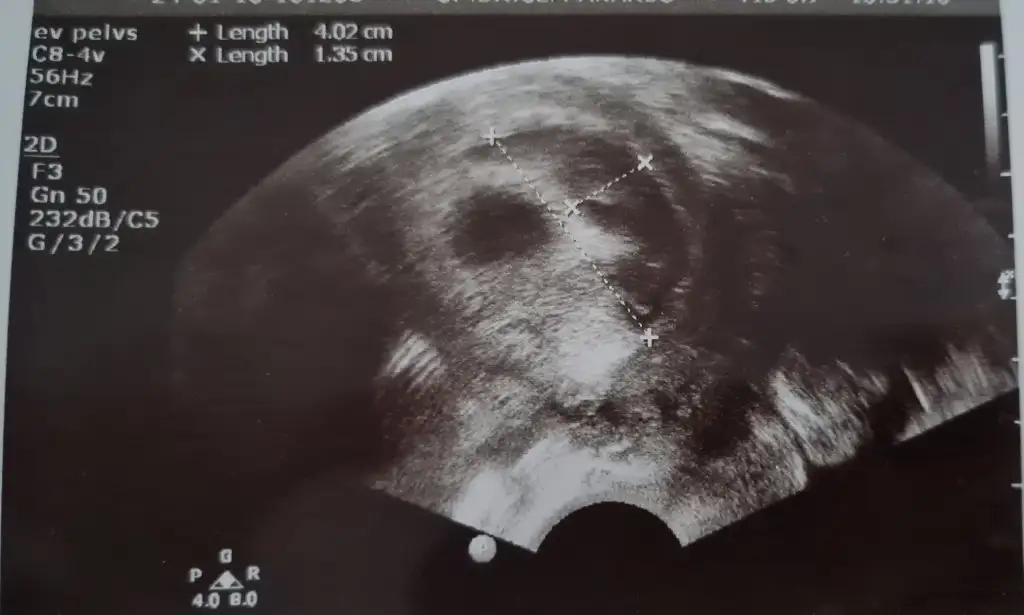

Geçmiş olsun öncelikle ben de aynı durumu yaşadım kanama alanım 1cm di kese altında sizin kaç cm alanı ve nerde ?arkadaslar merhabaalar yasayan varsa bi yardimci olabilirmisiniz 9 aralikta 5. gun embiriyosu transferi oldum taze transfer suan 7+4 teyiz 5+4te yolku gorduk bebisi ve kalbi duyucaktik carsamba gunu 7+2 ken ama sali gunu gece ani bi kanamayla hastaneye gittik adet kanamasi gibi ama temiz kan renginde yogun bi kanamam oldu ve hem kucuk hemde asiri buyuk el kadar ve avuc ici kadarda degisen kocaman cigere benzer pihtilar geldi ama agri sizi yoktu kalp atisini duydum gelisiminede iyi dedi ama kanama alanim cok buyukmus gorsel ekliyorum ben yumurta toplamadan beri progestan 200 luk fitil seklinde gunde 3 tane aliyodum simdi progestan dex ekledi gunde 1 kere seklinde benim gibi durum yasayip gecen var mi kalbim sıkışıyo o kadar kahroldum ki olumlu dusunemez oldum

altinda falan diye bi ibare yapmadi ama resim ekledim ilk resimde kesenin saginda tarali alan boyutta 4.2cm uzunlukta genislik 1.35cm doktorum dediki hastalar kanamadan korkar ama ben kanamasini severim cunku icerde basinc olusturmaz dedi kanama biraz kesildi gibi 2. gun temiz kan ara ara yine geliyodu ama bugun hep eski kan seklinde nokta gibi geldiGeçmiş olsun öncelikle ben de aynı durumu yaşadım kanama alanım 1cm di kese altında sizin kaç cm alanı ve nerde ?